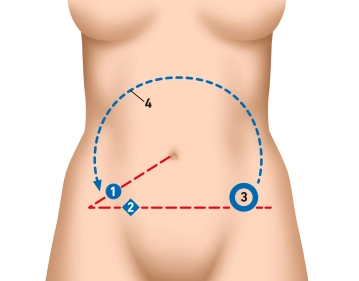

Hoje, a apendicectomia laparoscópica é realizada rotineiramente na Alemanha. As vantagens da laparoscopia são óbvias e prevaleceram sobre a abordagem aberta. Comparada à cirurgia aberta, há uma estadia hospitalar mais curta e tempo para retorno ao trabalho, menor taxa de infecção de ferida e morbidade e mortalidade gerais mais baixas. No entanto, há um tempo de operação mais longo e custos mais altos.

Outra vantagem da laparoscopia é a possibilidade de explorar a cavidade abdominal para excluir diagnósticos diferenciais, como adnexite/diverticulite de Meckel. Uma apendicectomia incidental é possível na ausência de contraindicação, pois, apesar de um apêndice macroscopicamente inconspícuo, histologicamente pode haver apendicite ou outras patologias, como endometriose, neoplasia, obstrução por apendicolitos ou parasitas.

Em casos justificados (por exemplo, diagnósticos diferenciais ginecológicos, suspeita de diverticulite sigmoide), a indicação para laparoscopia exploratória pode ser feita em suspeita de apendicite.